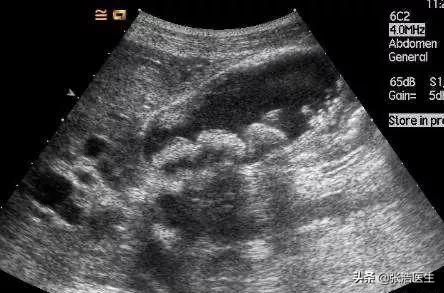

Ci-dessus, une échographie montrant la présence de plusieurs calculs de taille variable dans la vésicule biliaire.